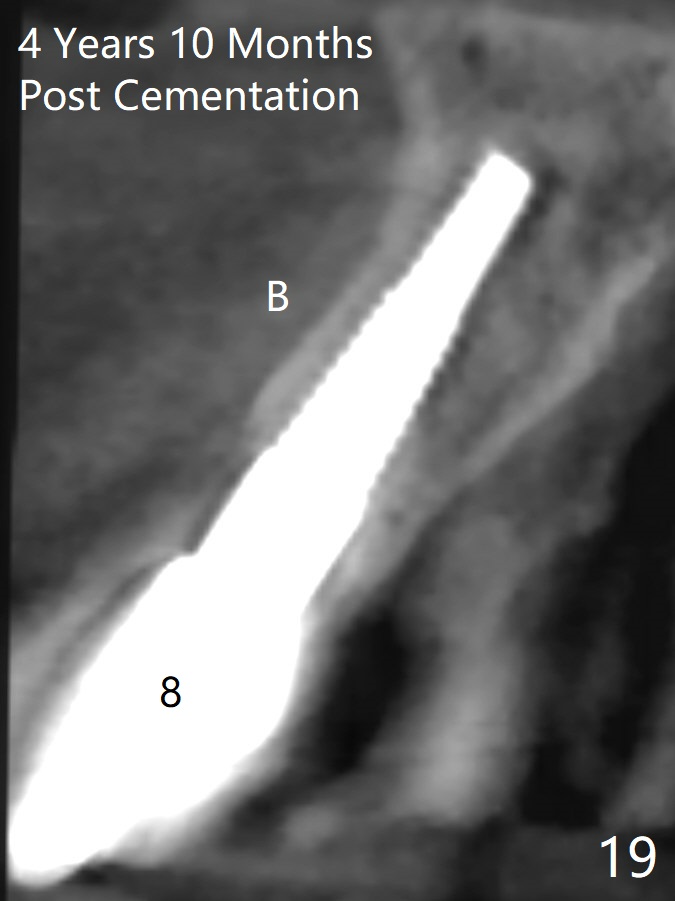

These two anterior implants remain stable 2 months 20 days postop, since one of the immediate provisionals has incisal chip (Fig.11 *) while both of them are splinted (<) to increase retention. There is no complain about paresthesia around the incisal papilla due to separation of the nasopalatine nerve. Mesiodens sockets disappear 7 months postop (Fig.13). There is no bone loss 2 years 9 months postop (Fig.14 panoramus) or 4 years 10 months postop (Fig.15,16 CT). The buccal gingiva is reddish and swollen with bleed on probing and history of pain 7 years post cementation (Fig.17). There is no bone loss in PA (Fig.18). The buccal plate at #9 is thinner than that at #8 4 years 10 months post cementation (Fig.19,20).